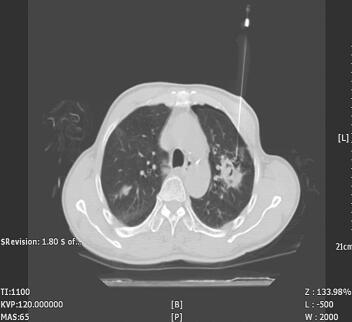

入院第7日(5月30日)血培养出大肠埃希菌,对头孢哌酮-舒巴坦钠敏感,加用头孢哌酮-舒巴坦钠(1∶1)2g,静脉滴注,每天2次;为明确肺部病变性质,于当日CT引导下行经皮肺穿活检术(图3),病理切片特染结果:抗酸染色找到多量抗酸杆菌;金胺O染色找到少量抗酸杆菌;PAS染色未找到真菌;PAM-Masson染色肉芽肿性炎伴大片干酪样坏死;抗酸及金胺O染色找到多少不等抗酸杆菌。患者入院第13日,无不适主诉,生命体征稳定,多器官损害已恢复,转结核科规范抗结核治疗。

图3 入院第7日CT引导下经皮左肺结节穿刺活检

最后需要注意的是患者肺部感染的诊疗。在发生糖尿病急性并发症的患者中往往合并感染,其中肺部感染的病原体可能是常见的社区性感染病原体,此时对于既往健康人群可能只引起轻微的上呼吸道感染,但糖尿病患者则可能因此发生严重并发症;从另一个角度来讲,因为是糖尿病患者,因此也易于发生一些机会致病菌或免疫力低下患者易感染微生物的感染,如结核分枝杆菌、真菌等,其中糖尿病患者肺结核患病率10倍于普通患者。因此必须在经验性治疗的基础上尽量明确感染病原体以便进行针对性治疗。本例患者初期给予了亚胺培南和抗真菌药物治疗,后根据血培养结果给予针对性敏感药物头孢哌酮-舒巴坦钠治疗,但从CT提示多发斑片状结节影,为进一步明确诊断,于CT引导下肺穿刺,最终明确病灶为肺结核,在乳酸性酸中毒、脓毒性休克得到纠正,细菌性肺炎治疗好转后开始进行系统抗结核治疗。